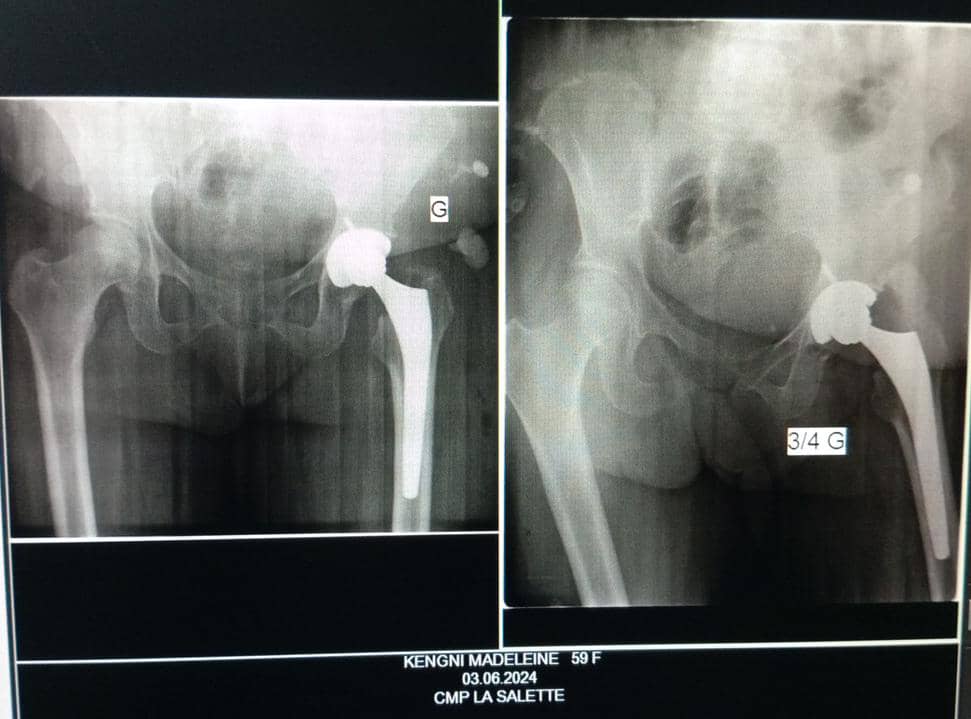

Arthroplastie totale de hanche

L'arthroplastie totale de hanche est une intervention chirurgicale visant à remplacer l'articulation de la hanche par une prothèse.